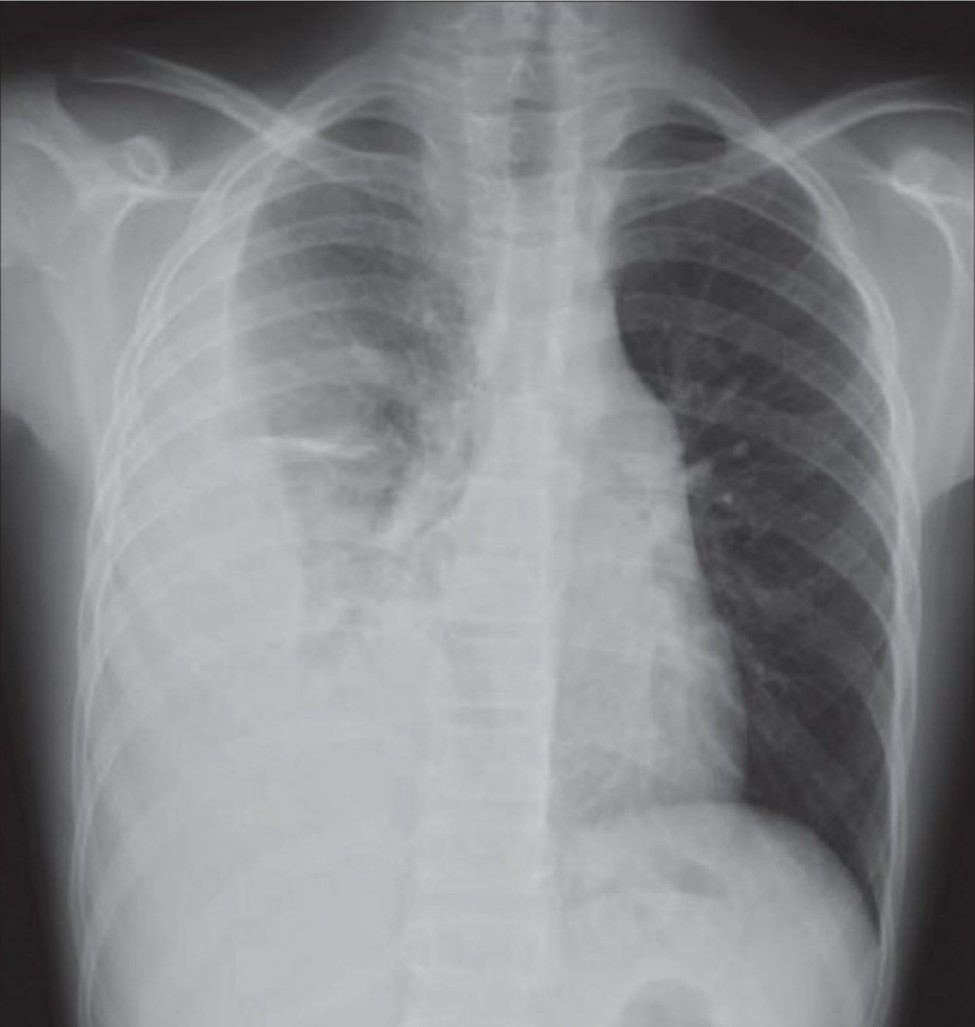

Pneumonia

A 30-year-old homeless male presents to your tertiary ED with a productive cough, fever, shortness of breath and haemoptysis. He …